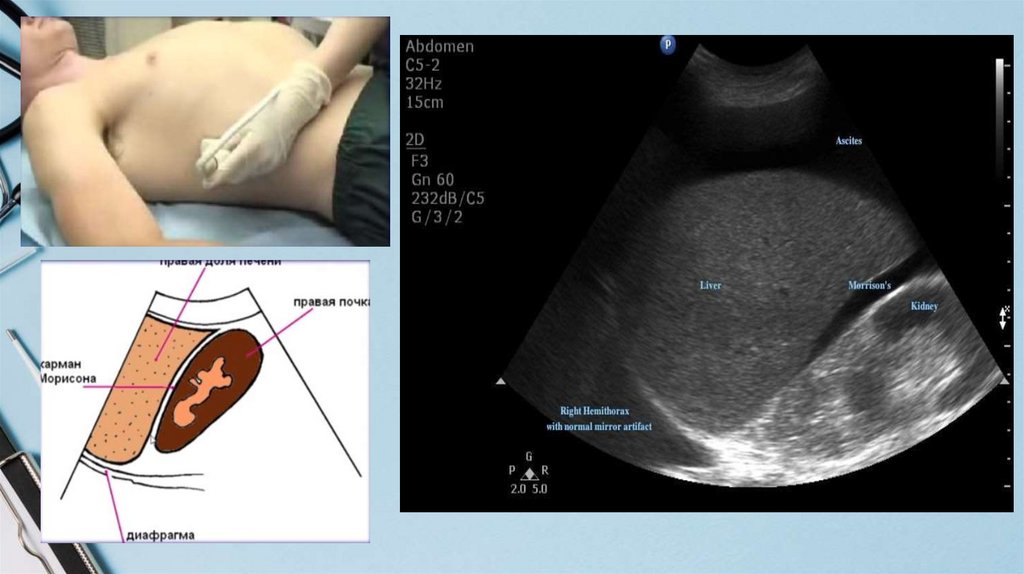

Slide title

22. Плевральный выпот